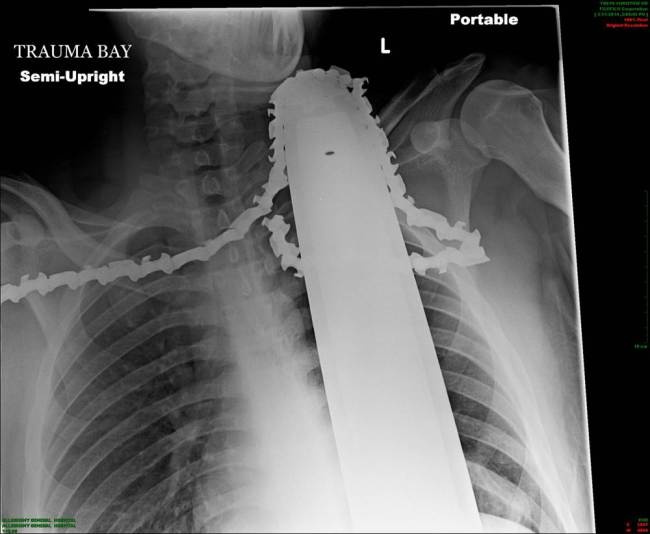

Αυτή η απίστευτη ακτινογραφία που θα δείτε, απεικονίζει πόσο κοντά στο θάνατο έφτασε ένας 20χρονος από το Πίτσμπουργκ όταν το πριόνι που κράταγε και έκοβε το δέντρο, του έφυγε από τα χέρια και απλά κόλλησε στο λαιμό του!

Ο Τζέιμς όπως λέγεται το παρολίγον θύμα, δήλωσε : «Ήταν απλά ένα φρικτό ατύχημα. Θα μπορούσε να συμβεί σε οποιονδήποτε που κόβει ένα δέντρο ». «Το αλυσοπρίονο ήρθε από πίσω μου και κόλλησε στο λαιμό μου».

Οι γιατροί είπαν ότι στο συγκεκριμένο σημείο υπάρχουν πολλές αρτηρίες αλλά το πριόνι έκοψε απλά έναν... μυ!